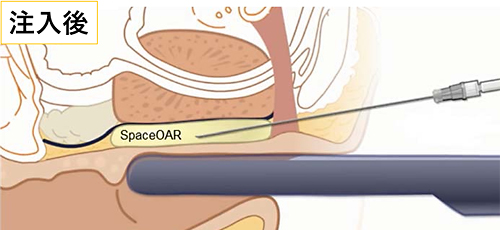

放射線の影響は距離が離れれば低減します。そのため、当院では前立腺と直腸の間にゲル状の物質を挿入し、前立腺と直腸の間を1.0~1.5cm離すことで直腸被曝を低減させる処置として、『直腸周囲ハイドロゲルスペーサ・SpaceOAR®』の留置を行っています。

- 注射針の位置を超音波画像で観察し、針先が直腸周囲脂肪組織の中にあることを確認し、生理食塩水を少量注入して空間を作成。その後にSpaceOAR®ハイドロゲルを前立腺と直腸壁の間(Denonvilliers筋膜 (腹膜前立腺筋膜))と直腸前壁の間)にスムーズに連続注入します(図:注入後)。

直腸に高い線量がかからないようにします。